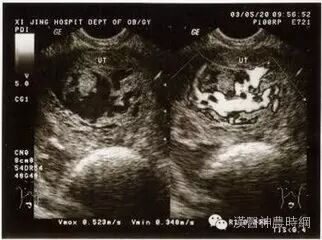

1.流产:葡萄胎病史与先兆流产相似,容易混淆,先兆流产有停经,阴道流血及腹痛等症状,妊娠实验阳性,但葡萄胎时多数子宫大于相应孕周的正常妊娠,HCG水平持续高值,B型超声图像不见胎囊及胎心搏动,而显示葡萄胎特点。

2双胎妊娠:子宫大于相应孕周的正常单胎妊娠,HCG水平也略高于正常,可与葡萄胎相混淆,但双胎妊娠无阴道流血,B型超声检查可以确诊。

3.羊水过多:一般发生于妊娠期,若发生于妊娠中期,因子宫迅速增大,需与葡萄胎相鉴别,羊水过多时无阴道流血,HCG水平在正常范围,B型超声检查可以确诊。